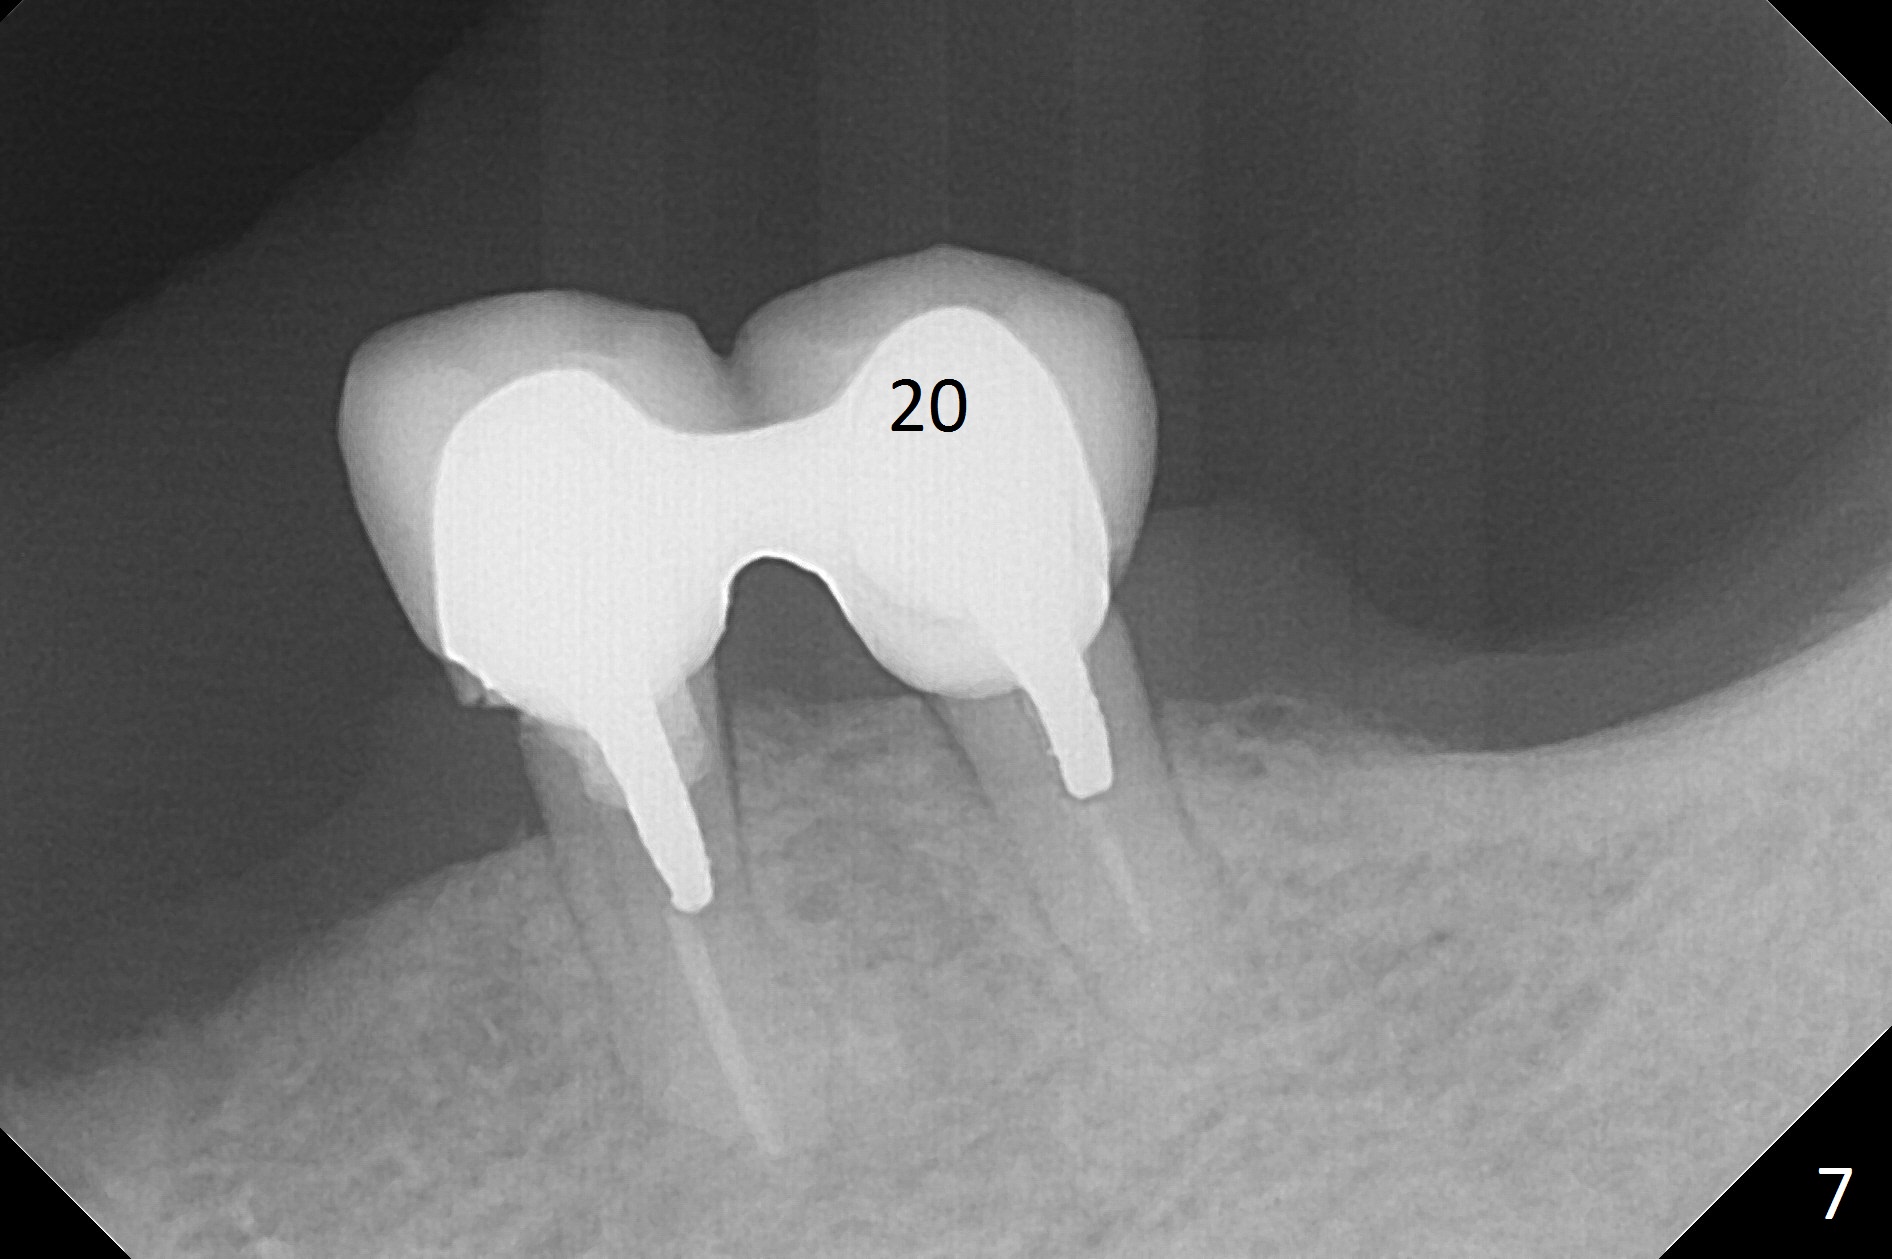

A 62-year-old woman has poor dentition (Fig.1). The most critical area is the upper left anterior: #9-11, which were extracted 4 months earlier (Fig.2). Implants will be placed at #9 and 11 with fabrication of a provisional bridge (Fig.3). After incision, use Magic Split to start bone expansion, followed by micro-osteotomes 1 and 1.5 mm and Magic Osteotomes 3 and 3.8 mm. If the transition between 1.5 and 3 mm osteotomes is not smooth, apply RT2. Place the smallest bone-level implants (for hybrid denture in the future) with gold coated abutments. There should be no interference with or without the partials and in and out. Next step should be removing splinted crowns at #26 and 27 (Fig.1), RCT for #27 and immediate implant at #26 (Fig.5,6 Metronidazole). In fact the splinted crowns at #26 and 27 were lost last week. The patient thinks that she needs 2 implants. The next one is to remove the crown at #5 for RCT (Fig.4).